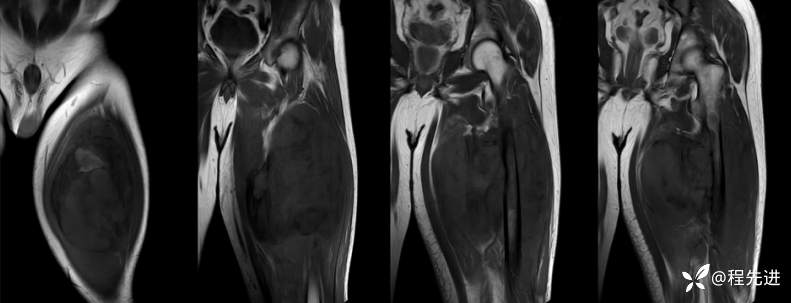

MR

T1

T2